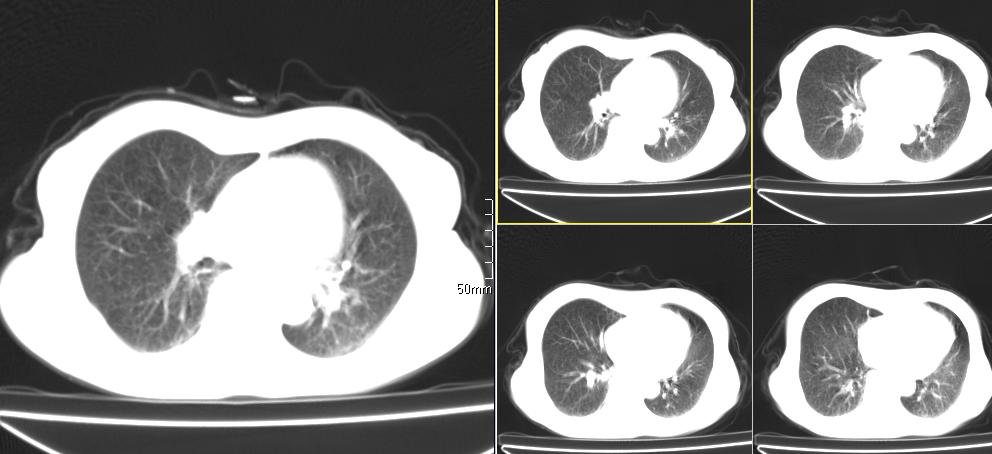

标题: CT26857:女,60岁,胃部不适前来就诊,不咳嗽,乏力,胸椎 [打印本页]

1、胸椎有骨质破坏伴周软组织,考虑胸椎转移。2、考虑左肺上叶尖后段支气管开口区周围型肺癌可能。

中央肺癌

1、胸椎有骨质破坏伴周软组织,考虑胸椎转移。2、考虑左肺上叶尖后段支气管开口区周围型肺癌可能。建议行纤支镜检查!

1、胸椎有骨质破坏伴周软组织,考虑胸椎转移。2、考虑左肺中央型肺癌可能。

1)考虑左肺中央型肺癌。2)胸椎转移瘤不排除;建议行mri检查。